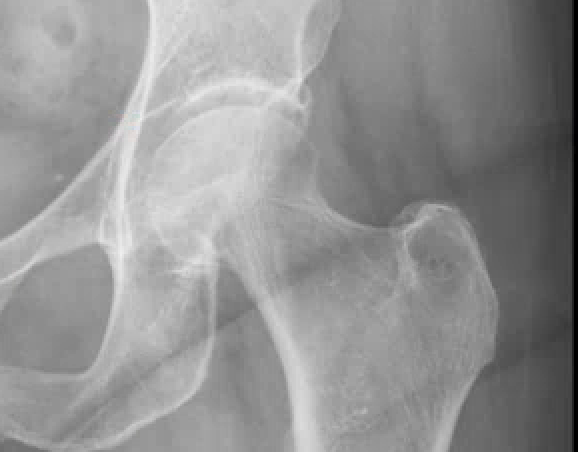

For this 74-year-old woman:

- Hip Joint => All is well. Phew..